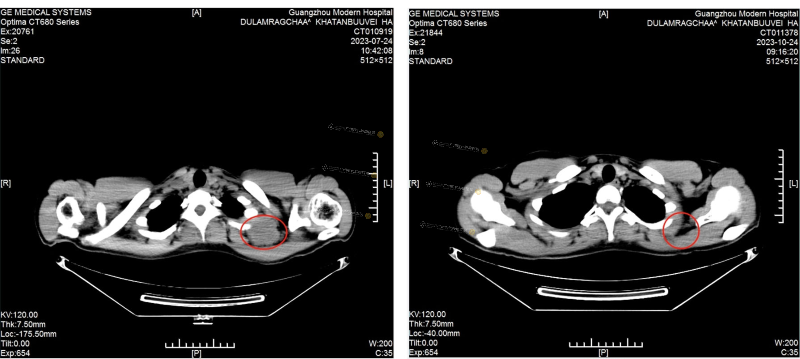

[The left picture shows the CT of the cervical lymphatic in July: the size of the tumor is about 50mm in diameter]

[The right picture shows the CT of the cervical lymphatic in October: tumor disappeared]